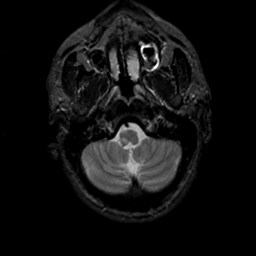

MR Study #18, July 21, 1991 -- Slice #6